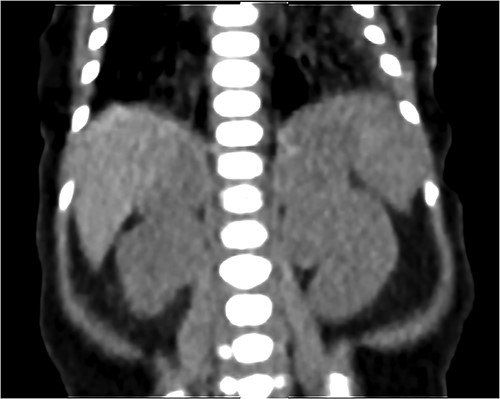

NCS was confirmed by elevated midnight cortisol level, dexamethasone suppression test and bilaterally enlarged adrenals on contrast-enhanced computed tomography (CT) scan as shown in Fig. 1. For NCS Metyrapone was introduced with a gradually increasing dose to 60 mg four times a day (QID). Though initially some symptomatic relief was accomplished, as a side effect baby developed a progressive increase in ALT to 1400. However, there was no long-lasting significant improvement in the Cortisol level. Cortisol remained very elevated at 2400 nmol as illustrated in Fig. 2, along with refractory hypertension, hyperglycemia and persistent failure to thrive (FTT) (weight 1.4 kg, length 36.5 cm at 7 weeks of age). Ketoconazole was not considered for treatment because of the elevated ALT.

Coronal CT scan with IV contrast shows a uniform lobular enlargement of both adrenals (red arrows).